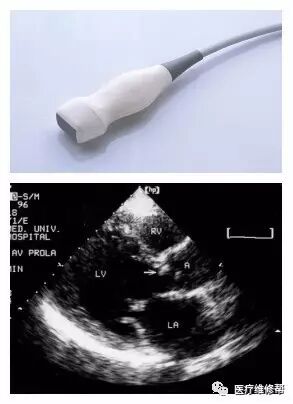

(二)一般常见的B超探头

1、凸阵探头3.5MHz 2、线阵探头3.5MHz 3、高频线阵7.5MHz 4、腔体探头6.5MHz 5、心脏探头3.2MHz 6、相控阵探头3.0MHz 7、三维探头3.5MHz